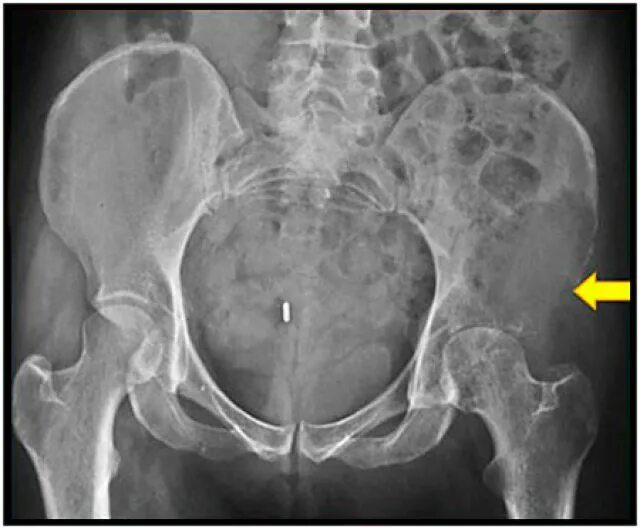

Метастазы в тазу